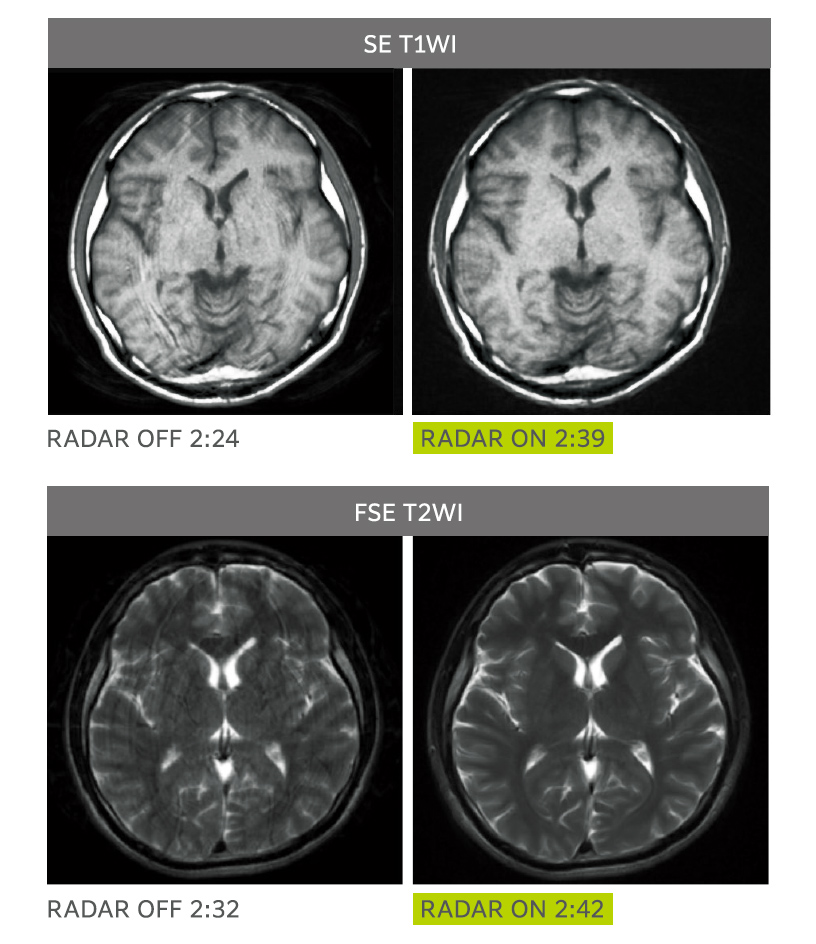

RADAR is applicable for routine head examinations

RADAR reduces motion artifacts and increases the ease of use by making it compatible with multiple sequences, all receiver coils and arbitrary cross sections. RADAR can be used in combination with high speed imaging as well. ECHELON Smart Plus's "All Around RADAR" is compatible with TOF sequences, GrE sequences and most of the sequences required for routine brain examinations.

RADAR has been applied to GrE sequences using a high-precision signal correction technology.

This has enabled the combined use with RADAR for all sequences required in routine brain examinations.